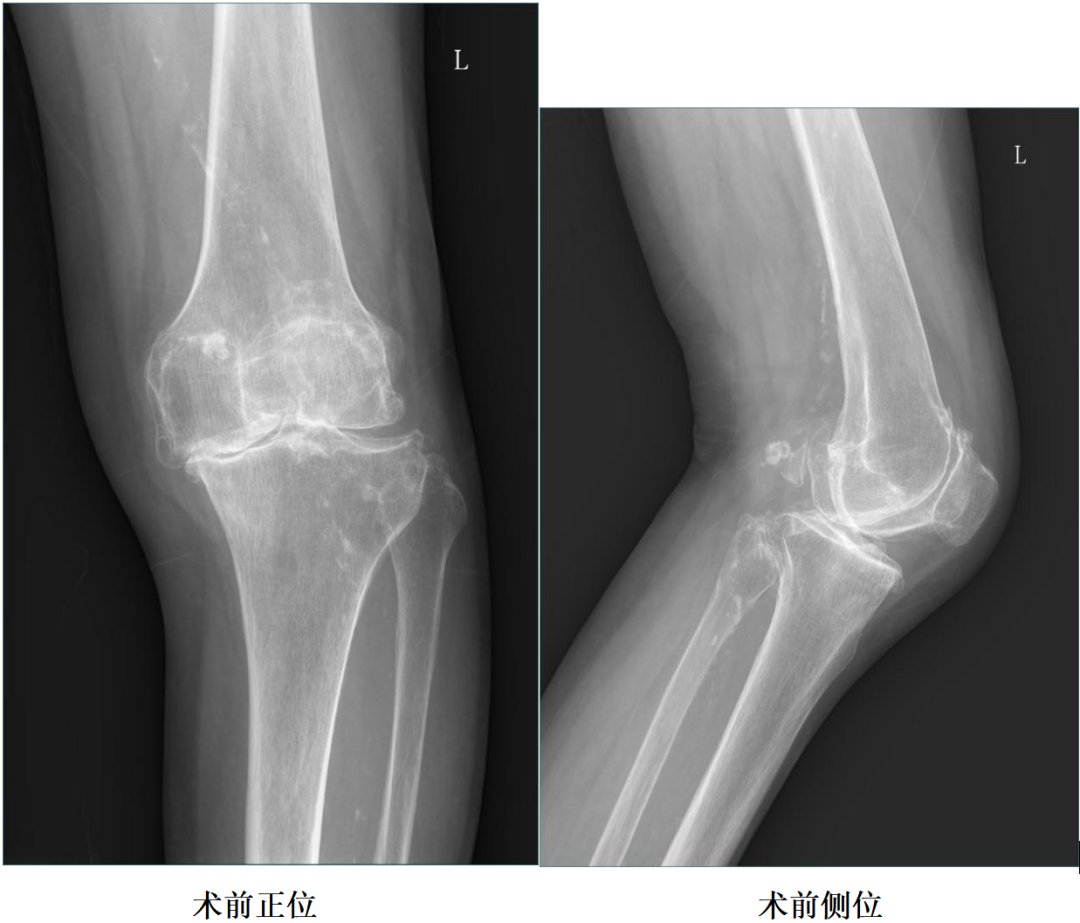

X-Ray:左膝内侧间隙明显狭窄,站立位内侧间隙消失,外侧间隙正常,膝关节稳定。

二、术前X片